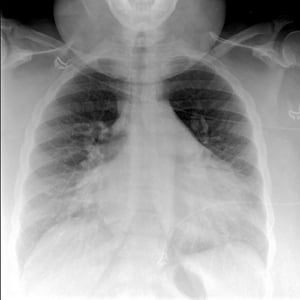

Chest Radiograph of a Patient with Pulmonary Edema

This radiograph shows bilateral perihilar patchy opacities in a "bat-wing" or "butterfly" pattern consistent with cardiogenic pulmonary edema. In this patient, the costophrenic angles are seen sharply, indicating the absence of significant pleural effusions.

© 2017 Elliot K. Fishman, MD.